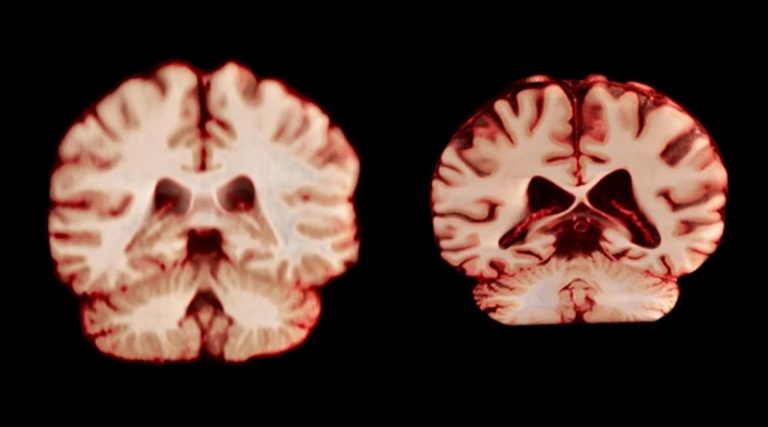

El cerebro de los hombres envejece más rápido: ¿por qué?